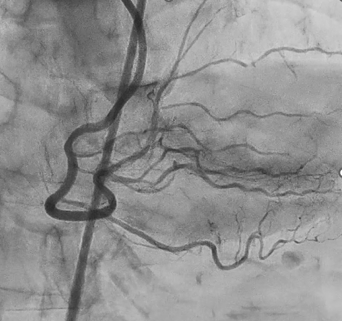

Coronary angiography revealed 100% occlusion of the right coronary artery (RCA) at segment #2, with collateral flow from the left anterior descending artery. The RCA was identified as the culprit lesion, and percutaneous coronary intervention (PCI) was planned. Engagement of the left coronary artery was achieved using a 7 Fr Launcher AL0.75 SH guiding catheter, and the lesion was crossed with a SION guidewire. A large amount of thrombus was observed in the coronary artery; therefore, thrombus aspiration followed by long balloon inflation using a 2.5 mm Ryusei balloon was performed. Although TIMI grade 1 flow remained in the #4PL branch due to residual thrombus, TIMI grade 3 flow was obtained in the #3–#4PD segments. The procedure was completed after intra-aortic balloon pump (IABP) insertion. After treatment for heart failure, coronary computed tomography performed on hospital day 21 showed thrombotic occlusion of the #4PD branch, for which a short course of direct oral anticoagulant (DOAC) therapy was initiated. Repeat coronary angiography on hospital day 33 demonstrated improved flow, although 99% stenosis persisted in the #4PL branch. As the RCA #2 lesion was identified as the culprit of acute myocardial infarction, a drug-eluting stent (Ultimaster Nagomi 3.0 ¡¿ 44 mm) was deployed in segment #2, and balloon dilation using an Agent 2.0 ¡¿ 30 mm balloon was performed for the #4PL branch, achieving successful revascularization.

This case demonstrates that staged revascularization is an effective strategy for acute myocardial infarction with high thrombus burden. Initial thrombus aspiration and balloon angioplasty, followed by delayed drug-eluting stent implantation after heart failure treatment, improved coronary flow. Careful evaluation using coronary CT and repeat angiography, along with a short course of direct oral anticoagulants (DOAC), aided thrombus management and led to favorable outcomes. This staged approach may benefit patients with delayed acute myocardial infarction presentation and complex thrombotic lesions, serving as a reference for similar cases.